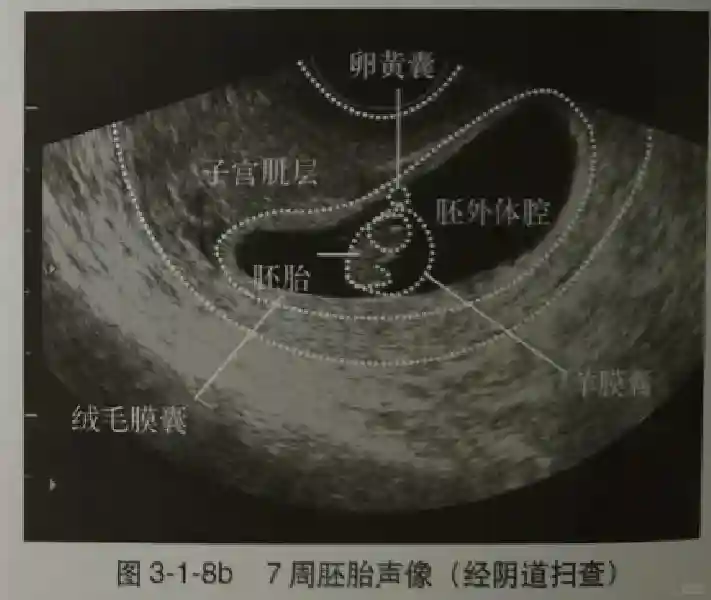

2??卵黄囊:是妊娠囊内第一个解剖结构,直径<7mm。表现为小环状,中央为无回声,囊壁薄,内透声好。卵黄囊位于胚胎旁胚外体腔内。卵黄囊通常在孕5-6周时出现,5-10周稳步增长,一般不超过7mm,至12周消失。妊娠囊的大小与卵黄囊之间有一定关系,妊娠囊平均直径> 8 mm 时,经阴道超声均应显示卵黄囊,妊娠囊平均直径> 18 mm 时,经腹超声均应显示卵黄囊。

3??胚胎:胚胎通常在6-7周时可以为超声显示,起初为胎芽,表现为卵黄囊一侧局部组织增厚,达到1 -2 mm 时才有可能为超声测量出来。达4-5mm时可见胎心搏动,相应孕周为6-6.5周,妊娠囊大小为13-18mm。胚芽长度≥7㎜时仍未见心管搏动,提示胚胎停止发育。胚胎的出现和妊娠囊直径的关系:妊娠囊直径> 16 mm 时,经阴道超声应显示胚胎。妊娠囊直径> 25 mm 时,经腹超声均应显示胚胎。

5??羊膜:早孕期羊膜囊菲薄,超声常不能显示。孕7周以后加大增益或者用高频超声可以显示羊膜。羊膜囊位于绒毛膜内,胚胎位于羊膜囊内。随着胚胎增长,羊水增多,羊膜囊增大,孕12-16周时,羊膜与绒毛膜全部融合,胚外体腔消失。宫腔线一侧内膜内一圆形增强回声区,中央有小囊状液性暗区,宫腔线局部突起变形,称蜕膜内征,用于判断早早孕。